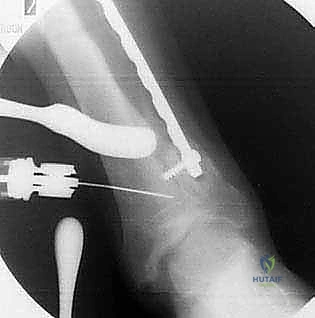

5. التثبيت الداخلي القوي (Internal Fixation)

بعد الوصول للزاوية المثالية التي تم حسابها مسبقاً، يتم تثبيت العظم بإحكام شديد باستخدام شرائح معدنية متطورة (Locking Plates) ومسامير من التيتانيوم. هذا التثبيت القوي هو ما يسمح للمريض ببدء الحركة والتأهيل مبكراً.